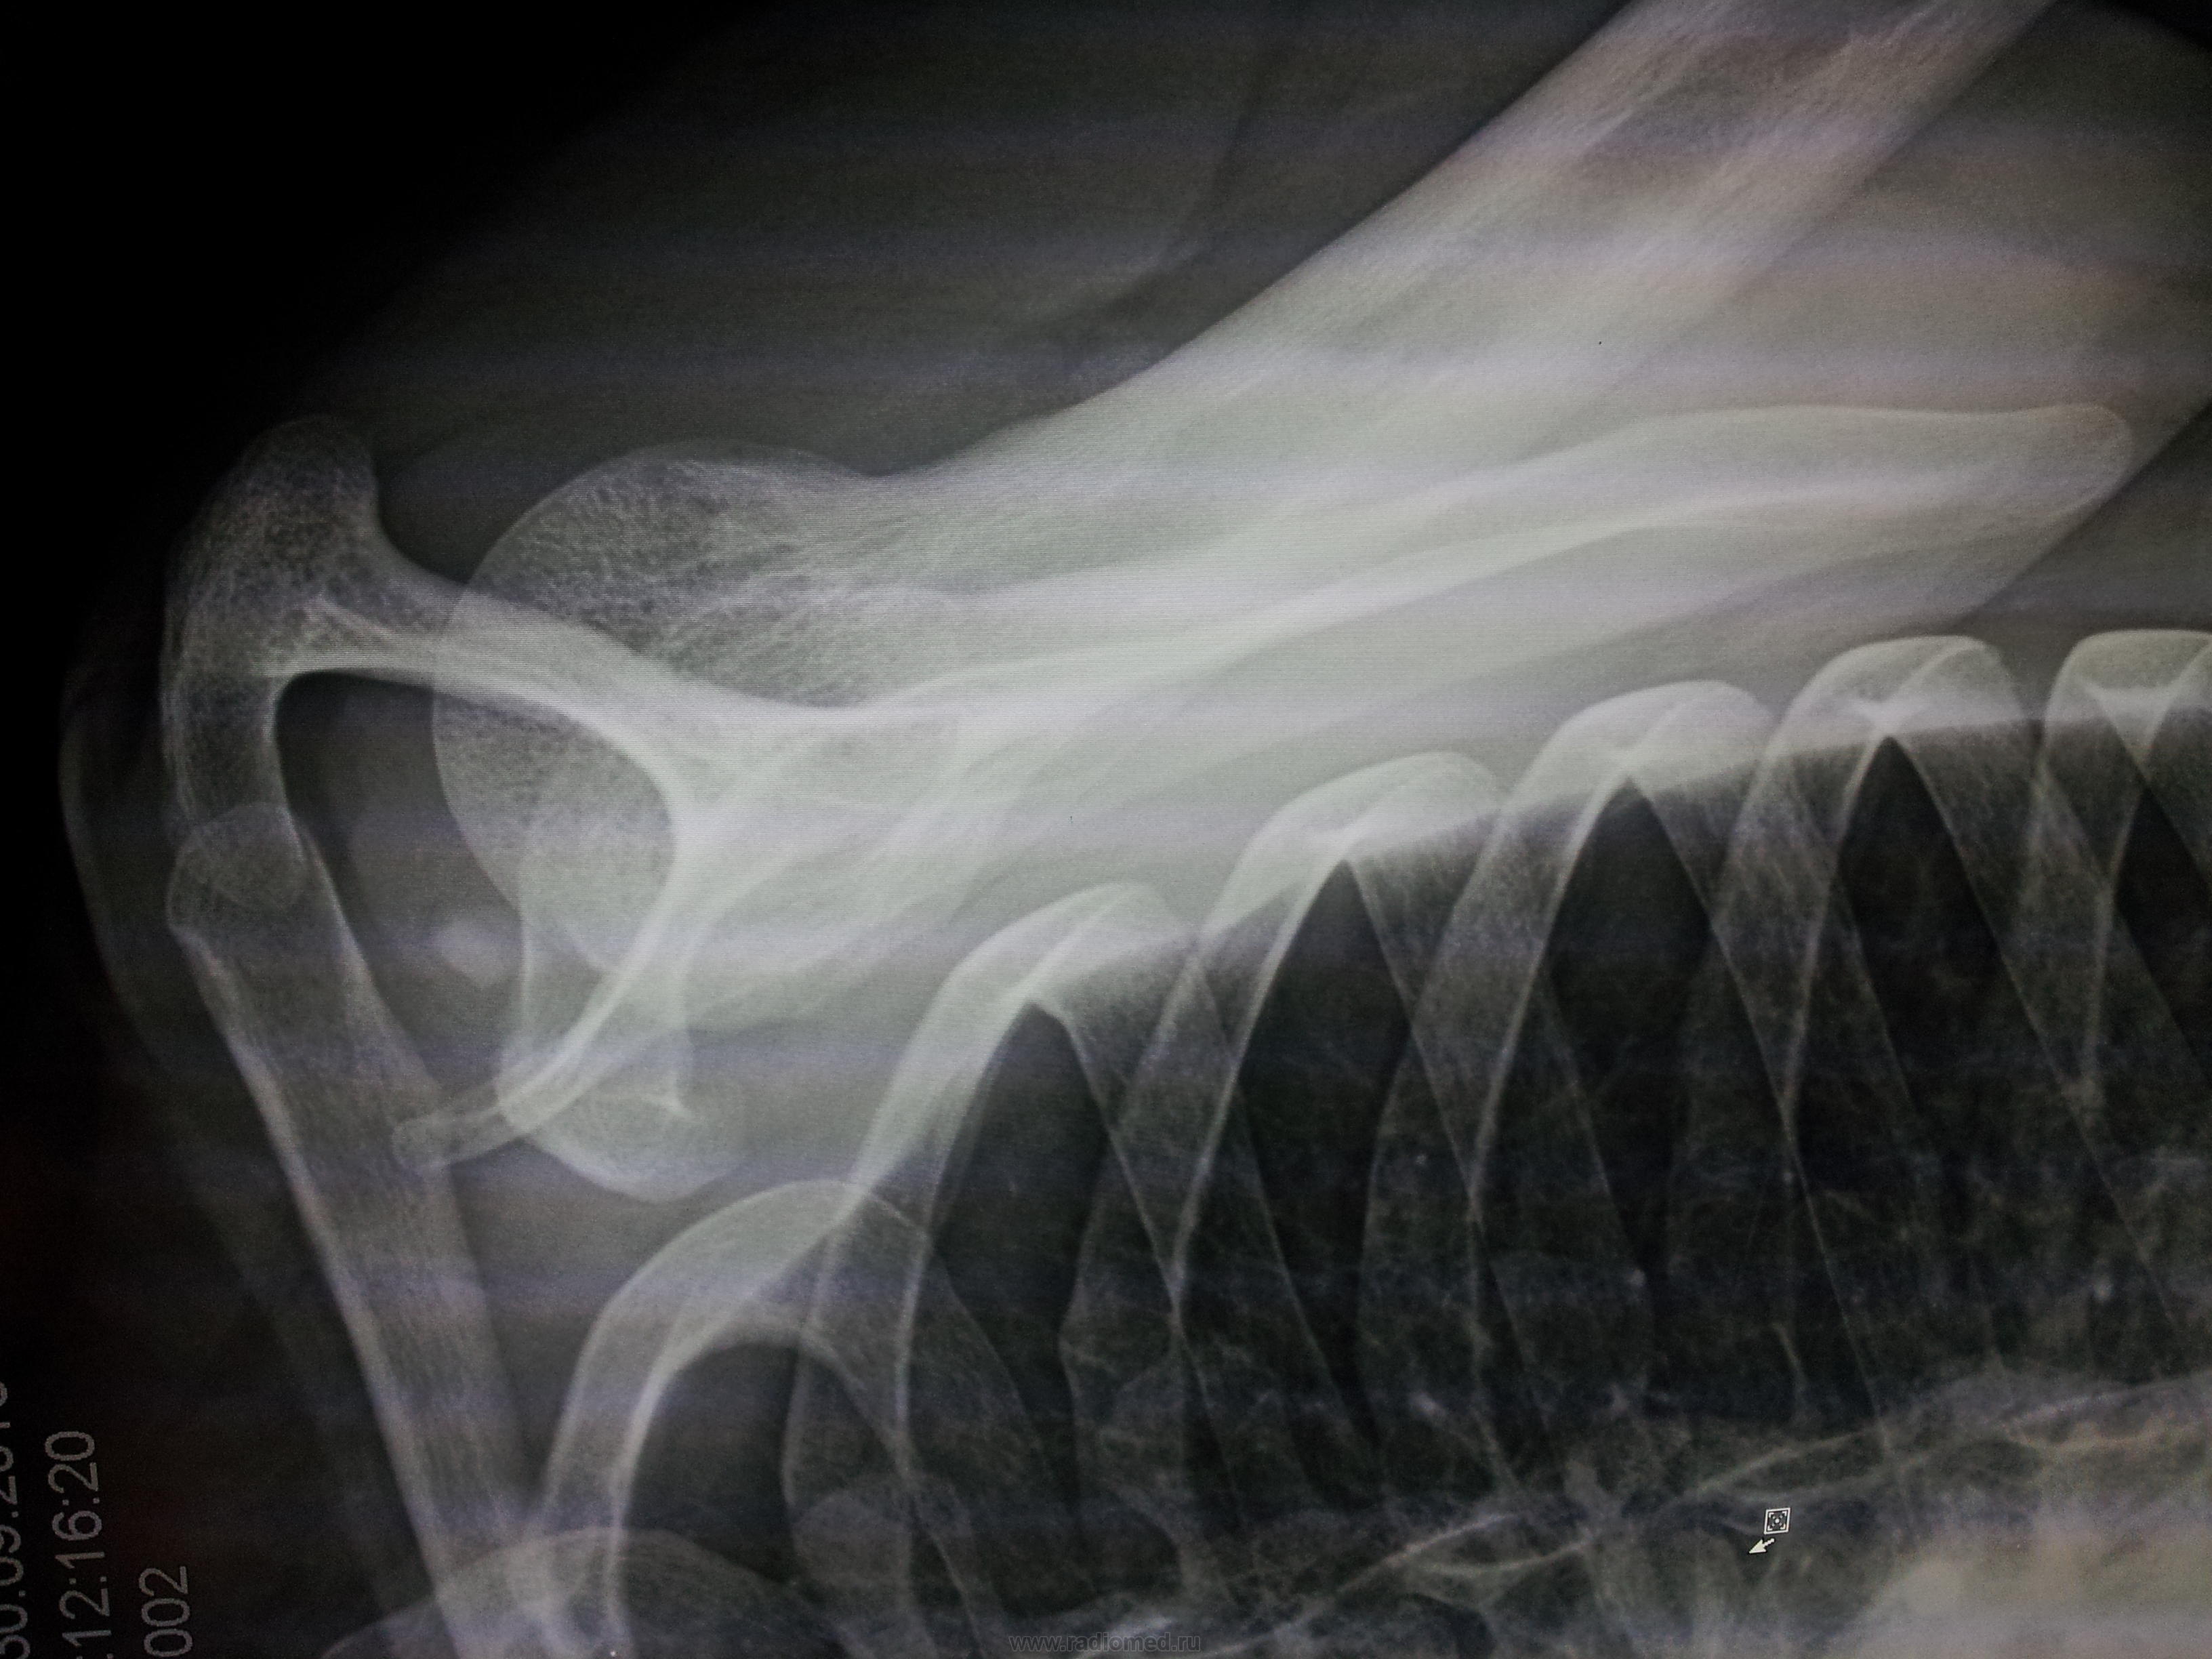

Проекции разные. На том, который второй - хондромное тело в суставе?

Есть участок обызвествления связки продольной мышцы. Перестройка в плечевой кости тоже есть. Но какая она? У пожилых может быть и добракачественная, гемангиомоподобная. Не знаю ваших возможностей дообследования. Есть возможность - отправьте на МРТ (в любом случае не помешает), нет возможности, сделайте другой сустав.

Настораживает необычная перестройка кортикального слоя всего диафиза плеча - утолщение и разволокнение - нет ли здесь болезни Пэджета?